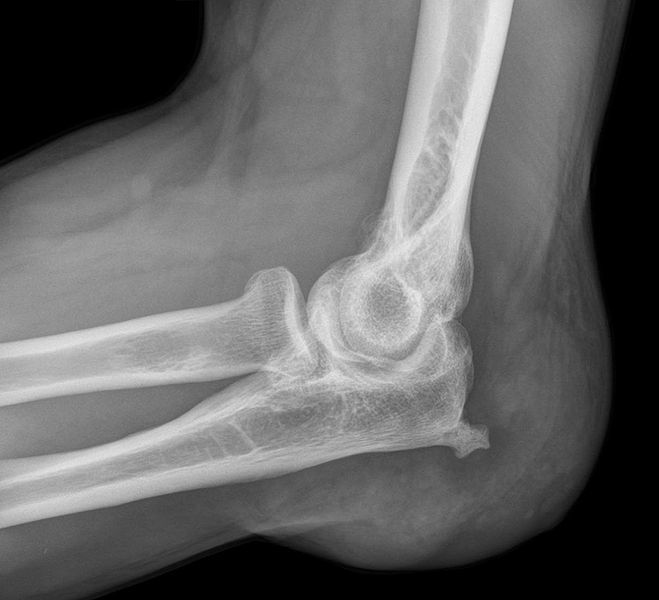

What is shown on the image?

A plain film radiograph showing soft tissue swelling (with associated bony spur) from olecranon bursitis.